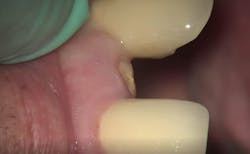

First visit: Extraction and immediate implant placement, immediate placement of the final abutment prepared intraorally, and then a provisional out of function.

The implant was allowed to heal for two months before impressions were taken. The final zirconia crown was delivered two weeks later (figure 6).